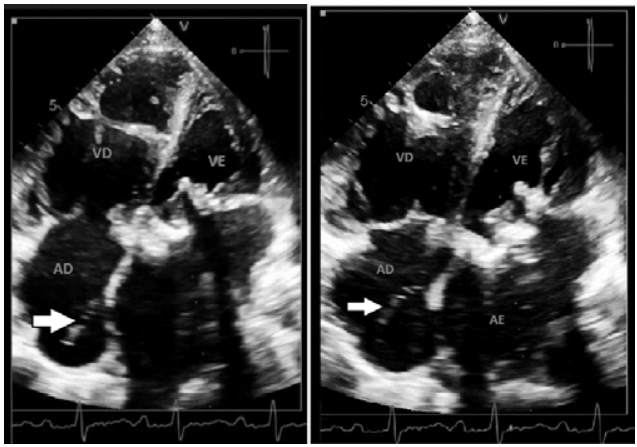

Paciente de 55 anos de idade, sexo feminino, em avaliação da prótese biológica em posição mitral com provável estenose, apresenta uma estrutura móvel em átrio direito (de acordo com a seta).

Com base nessa situação hipotética, assinale a alternativa correta que correlaciona a estrutura apontada pela seta e outro achado que pode estar associado à sua presença.

Imagem: arquivo pessoal.

Paciente de 48 anos de idade, sexo feminino, apresenta fibrilação atrial e sopro regurgitativo em foco mitral. Foi realizado ecocardiograma, o qual obteve as imagens abaixo.

Com base nessa situação hipotética, assinale a alternativa correta que apresenta o diagnóstico ecocardiográfico do mecanismo da insuficiência mitral e a classificação de Carpentier.